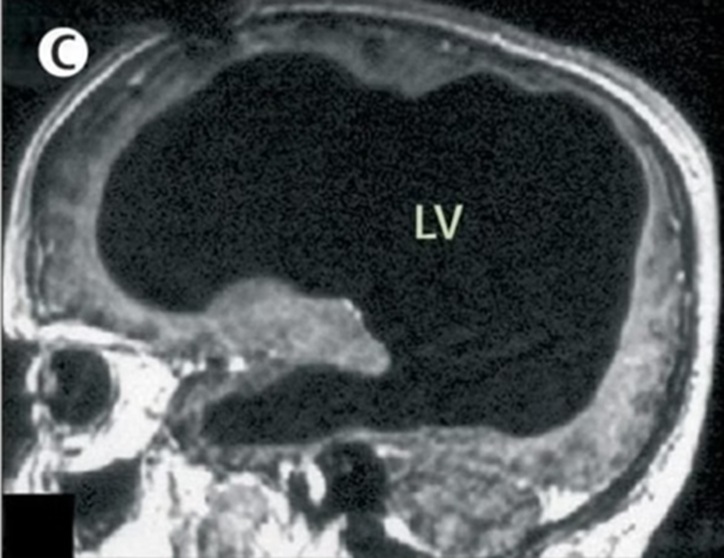

Os exames, no entanto, revelaram a condição rara: o cérebro estava reduzido a uma fina camada nas bordas do crânio, com ventrículos extremamente dilatados.

As tomografias e ressonâncias magnéticas mostraram dilatação severa dos ventrículos laterais, terceiro e quarto. O diagnóstico final foi hidrocefalia não comunicante.